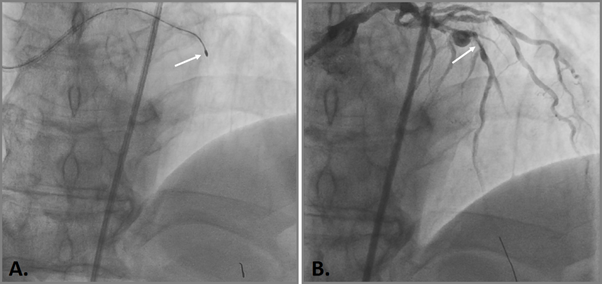

The patient underwent endovascular rotational atherectomy followed by stenting of the affected segments of the coronary arteries. The intervention was carried out under the control of optical coherence tomography (OCT). Initially, the right common femoral artery was punctured under local anesthesia and a 7F introducer was placed. Next, the guide catheter was placed at the mouth of the LCA. The coronarogram revealed 80% calcified stenosis in the terminal LCA OS with a transition to the proximal segment of the LAD and 90% calcified stenosis in the middle segment of the LAD (Figure 1). Using a microcatheter, a conductor was introduced into the apical segment of the LAD. Next, the destruction of calcified atherosclerotic plaques in the LCA and LAD was performed using the Rotablator system of rotational atherectomy (Figure 2), after which, under OCT control (Figure 3), predilatation of the stenotic areas of the LAD with a 2.25x15 mm balloon catheter was performed, followed by positioning and implantation in the area of residual stenoses in the middle segment of the LAD, the proximal segment of the LAD and the OS of the LCA of everolimus drug-eluting stents 3x38 mm and 4x38 mm, respectively. Then, post-dilatation of the stented segments with 3.5x20 mm, 4.5x15 mm balloon catheters and proximal optimization in the LCA OS with a 5x15 mm balloon catheter were performed, achieving a good angiographic result: blood flow in the TIMI-3 arteries. On the control image and OCT control, the stents were fully extended, no signs of dissection were detected, and no residual stenoses were found (Figure 4, 5).

Figure 2 Endovascular rotational atherectomy.

A. Rotational drill in the area of the stenosed middle segment of the LAD (white arrow); C. Angiographic result of a rotational atherectomy in the region of the middle segment of the LAD (white arrow).